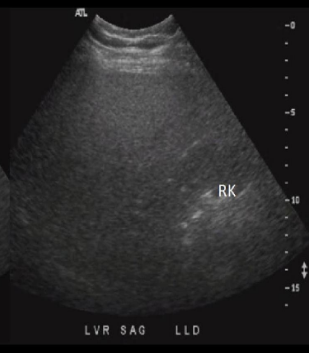

Identify this image.

Acute hepatitis